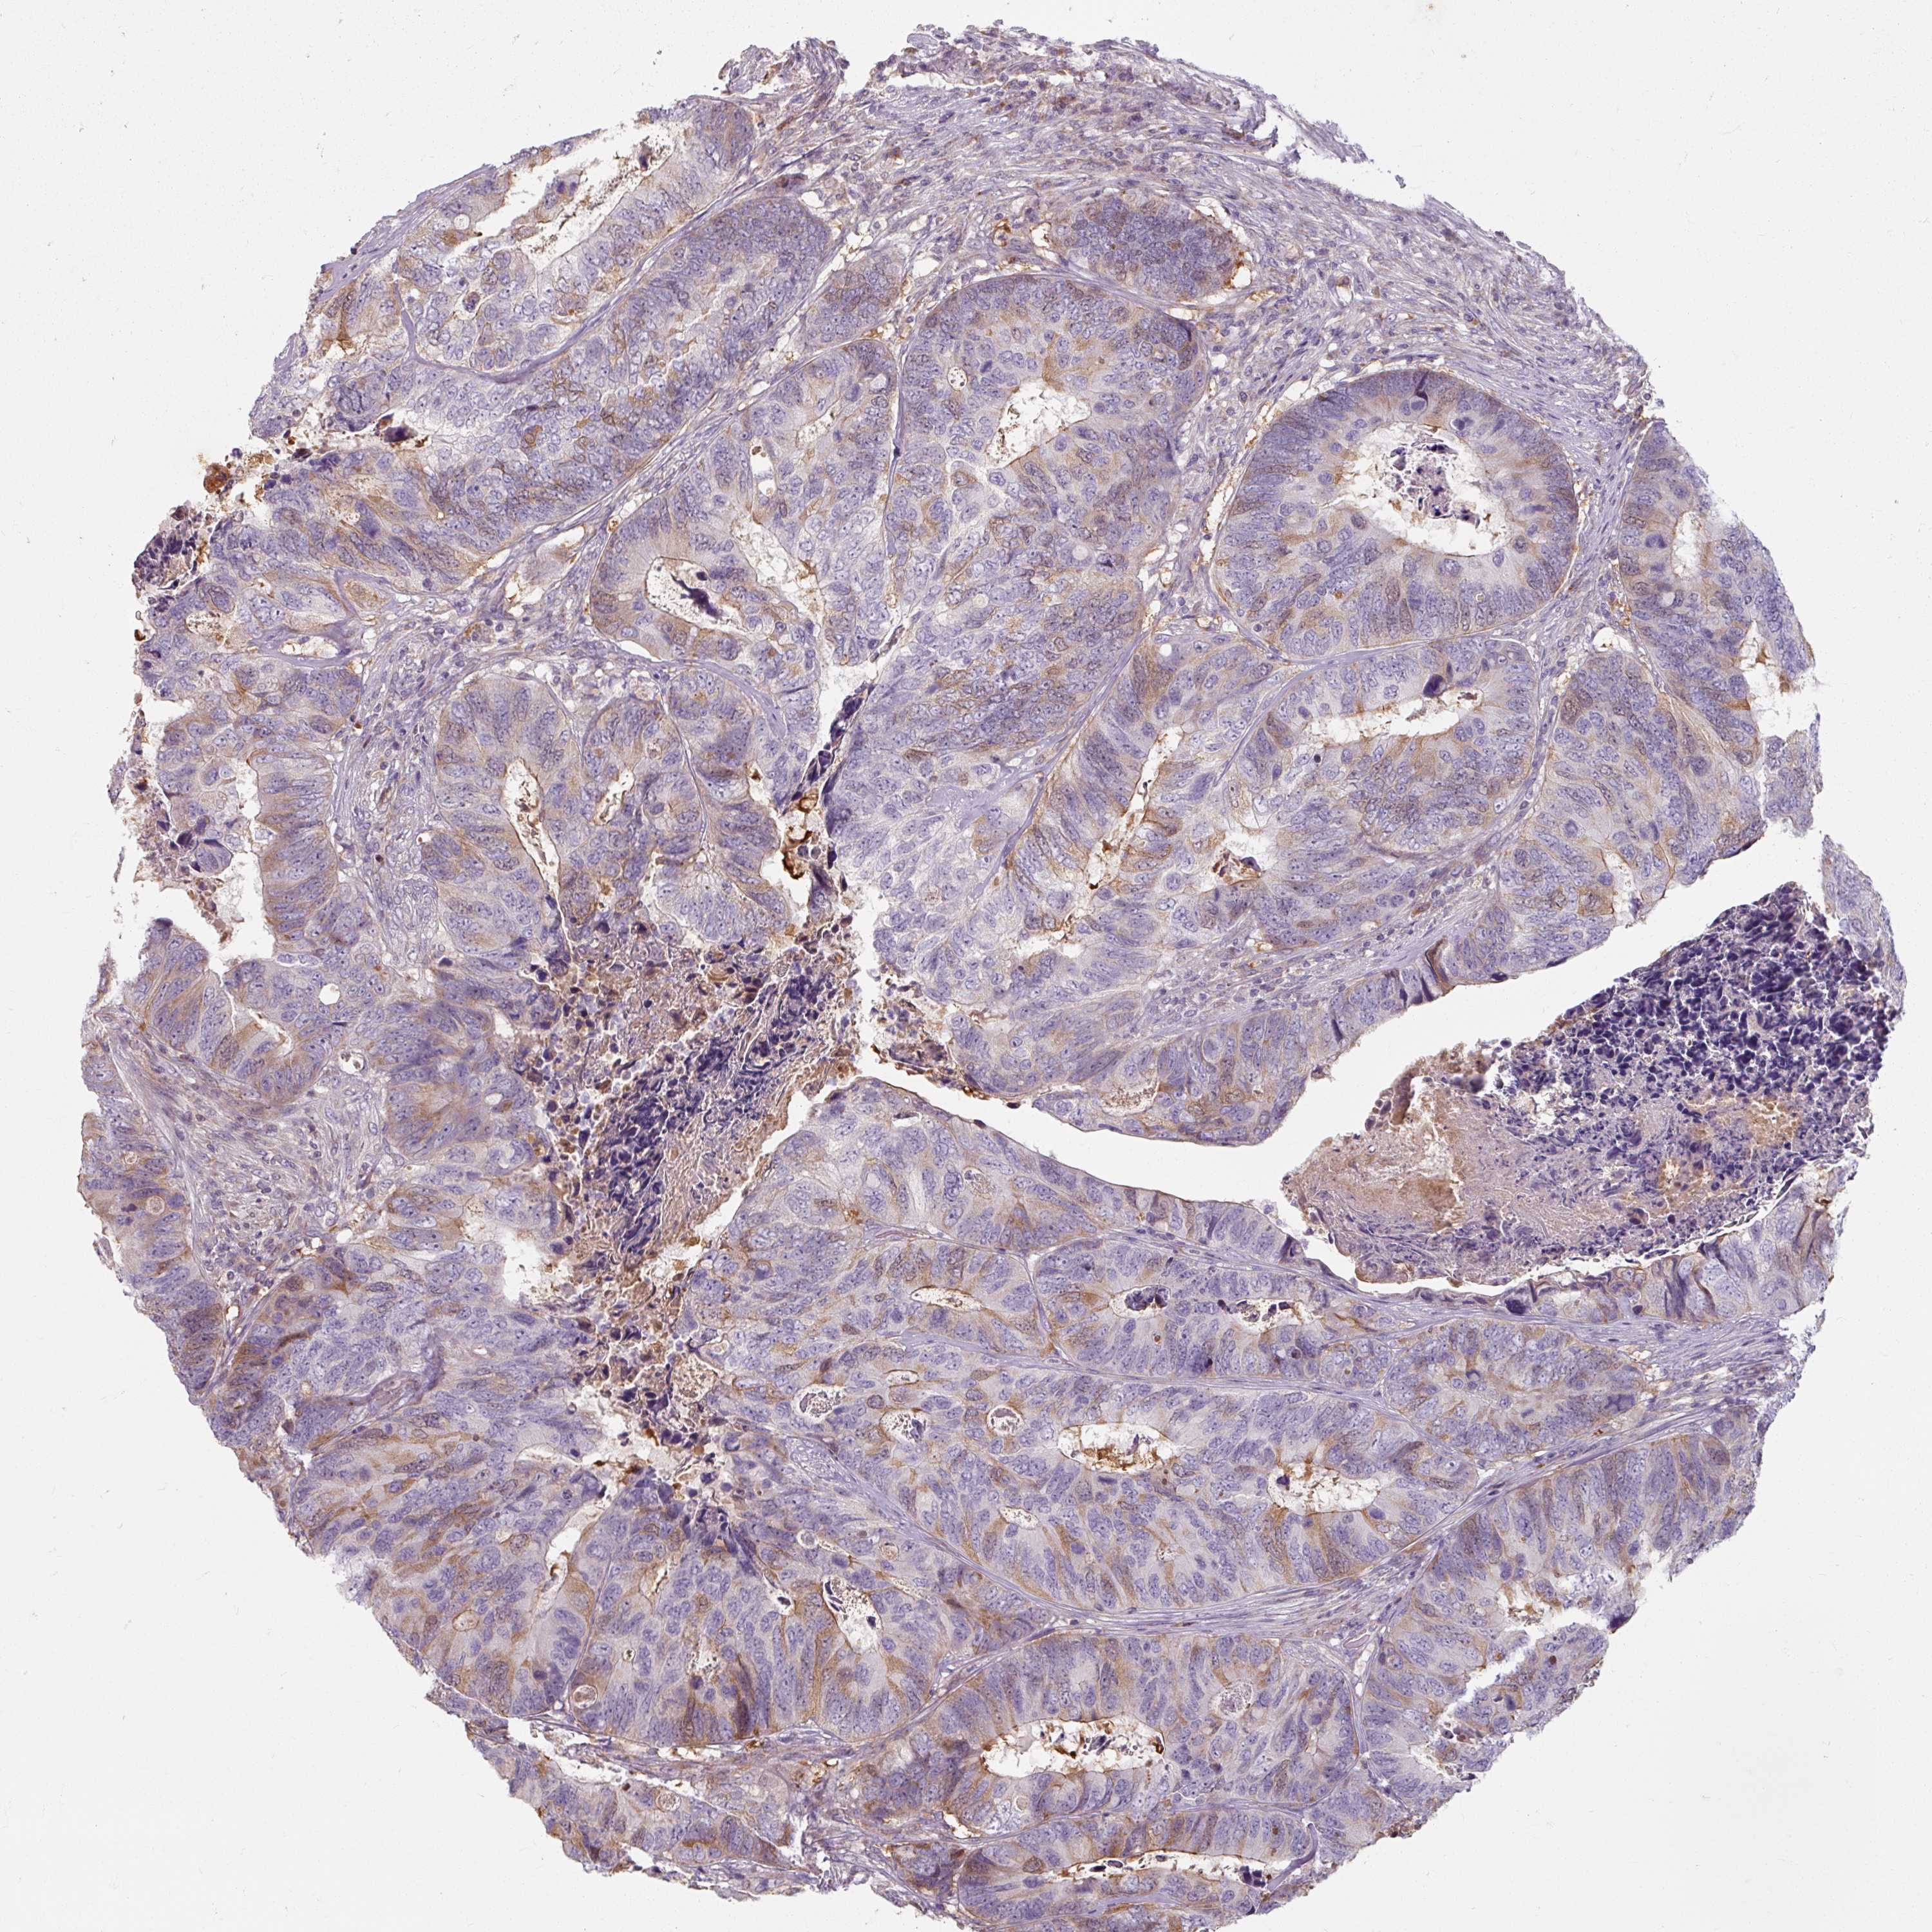

CANCER COLORECTAL CANCER Show tissue menu

Colorectal cancer

Human cancer

Colon adenocarcinoma